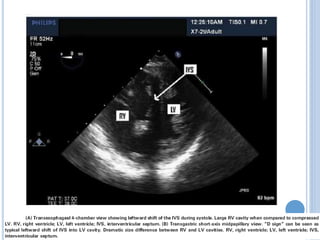

 Desplazamieno del septum IV (interdependencia

interventricular)

VENTRÍCULO DERECHO  VD dilatadoafecta el annulus de la válvula tricuspidea = insuficiencia  Exacerbación del estado de volumen del VD  Falla del VD  Desplazamieno del septum IV (interdependencia interventricular)  <volumen de fin de diástole VI= Falla cardiaca=perfusión tisular inadecuada